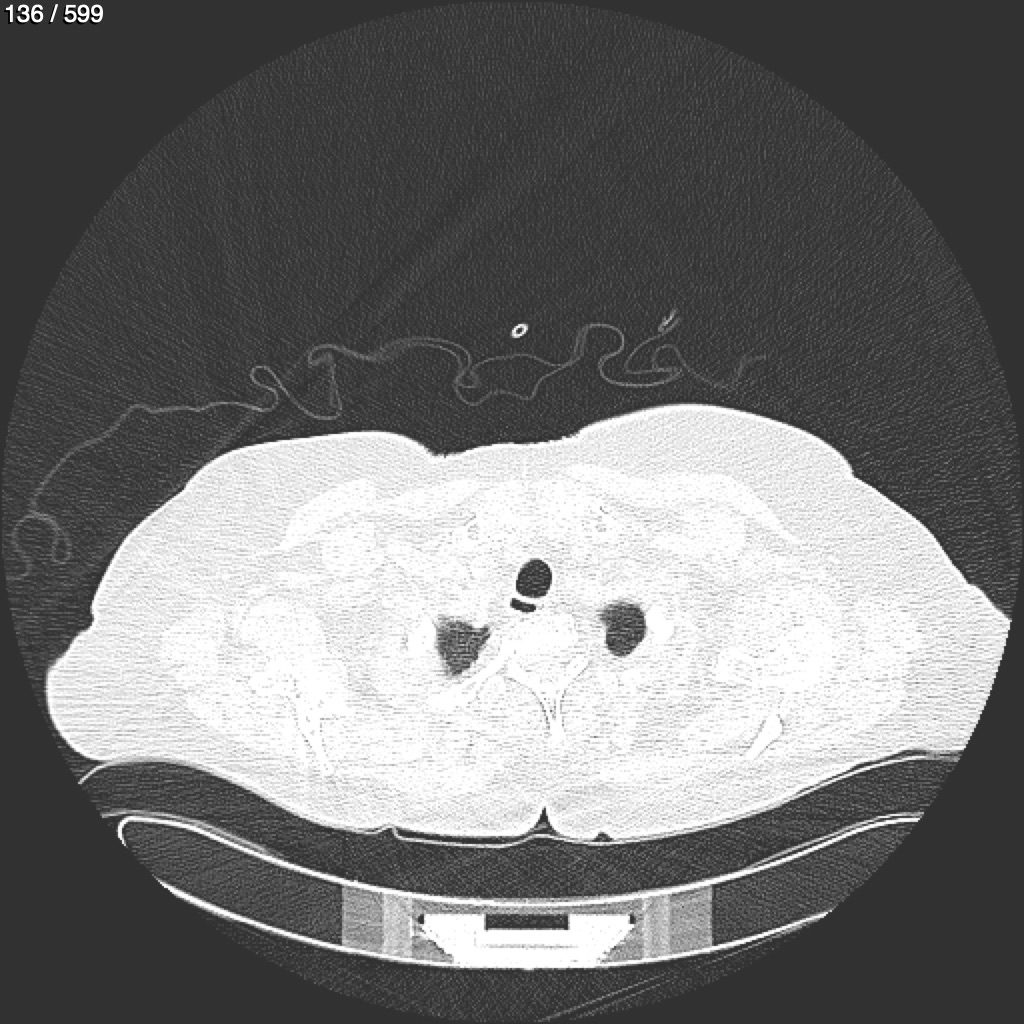

Home G​l​o​r​i​a​ ​G​l​a​d​y​s​ ​B​e​a​s​l​e​y​ ​-​ ​T​ó​r​a​x​ ​T​o​r​a​x​_​S​i​m​p​l​e​ ​(​A​d​u​l​t​o​)